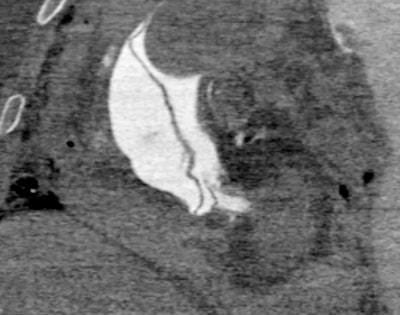

CT image shows type A aortic dissection.

CT image shows type A aortic dissection.Boyce: Some European centres, particularly in Switzerland, prefer a whole-body angiogram, and they use a contrast media injector because it requires about three litres of fluid to opacify the vessels. A group in Leicester, U.K., also uses a CT pump injector for this purpose -- the same as we do for clinical CT. I thought PMCT angiography may be difficult to interpret due to the presence of a lot of clots, but actually, you can often get decent images. Just like in any clinical practice, it's not always perfect. The specialty is still quite new, so no one knows exactly what the best technique is; everyone does it slightly differently. Overall, it's about getting the best images to provide the best diagnosis.